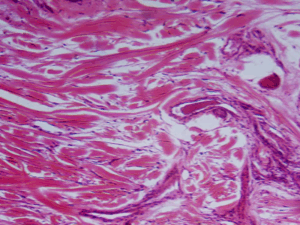

Nghiên cứu dược liệu: Bảo vệ buồng trứng & ấm tử cung

Sức khỏe buồng trứng không chỉ quyết định khả năng thụ thai mà còn ảnh...